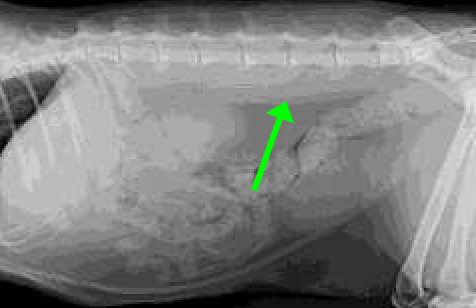

1.6, L5

Dog’s small intestine should be no wider than ____ x height of ____ body

12 mm

Cat’s small intestine should be no wider than ____ in diameter

ventral and right

A fat cat’s small intestines are usually displaced _______.

L7

Large intestine diameter should be less than or equal to the length of ___ on lateral view